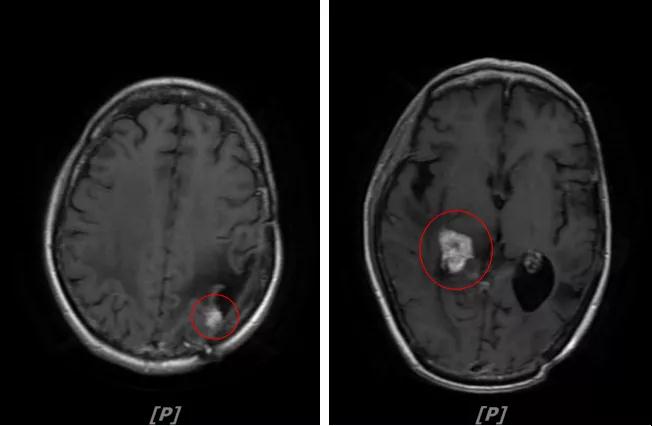

5. 病情第4次进展:2019年11月患者出现视野模糊等症状

头颅增强MR:左侧顶颞叶见片状T1WI低信号、T2WI高信号影,病灶大部信号接近脑脊液,增强后术区边缘左侧顶叶见结节状强化影,大小约10x8x11mm,较2019-03- 15MR老片大致相仿;右侧脑室三角区见结节样T1WI等低信号、T2WI不均匀稍高信号影,增强后不均匀明显强化,大小约24x18x20mm,较2019-03-15MR老片明显增大;两侧半卵圆区、侧脑室旁见较对称片状T1WI低信号、T2WI高信号影,增强后未见明显强化,较前片相仿;余脑室、脑池、脑沟大小形态可,中线结构向左偏移。

左顶颞叶转移瘤治疗后改变

右侧脑室三角区旁强化结节,较2019-03-15MR老片明显增大 左侧顶叶强化结节,较2019-03-15MR老片大致相仿

两侧脑室旁云絮状异常信号,考虑放疗后改变

患者三线治疗的PFS为14个月,2019年12月给四线治疗为“吡咯替尼+阿那曲唑”基础上联合曲妥珠单抗。

患者视野模糊等症状有所改善,继续定期复查。